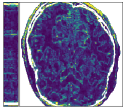

Figure 5 shows an example of a spatio-temporal regularization parameter-map which was estimated using the proposed approach for an acceleration factor of . The network estimates the regularization parameter-map to be pointwise relatively consistenly higher than the spatially required regularization. This result is in fact expected as the temporal dimension is the one for which the gradients of the images are the sparsest because of the high temporal correlation. Further, we see how the network consistently predicts both the spatial regularization as well as the temporal regularization to be less strong in the area where most of the movement is expected, i.e. in the cardiac region.

Figure 6 shows examples of the quantitative (magnitude) images of three of the 112 simulated inversion recovery measurements in the test dataset. We also show the regularization parameter-maps for regularization along the spatial directions and along the inversion-time direction generated by the network. The mean PSNR and SSIM of our proposed method is consistently higher for all considered acceleration factors, even compared to PDHG with regularization strength along spatial and inversion-time direction chosen by grid-search with access to the ground truth images (shown in Figure 8 and Table 2). The resulting parameter-maps after performing the regression on the reconstructed images are shown in Figure 7. Again, our proposed method results in the lowest RMS deviation from the ground truth images (Table 2).